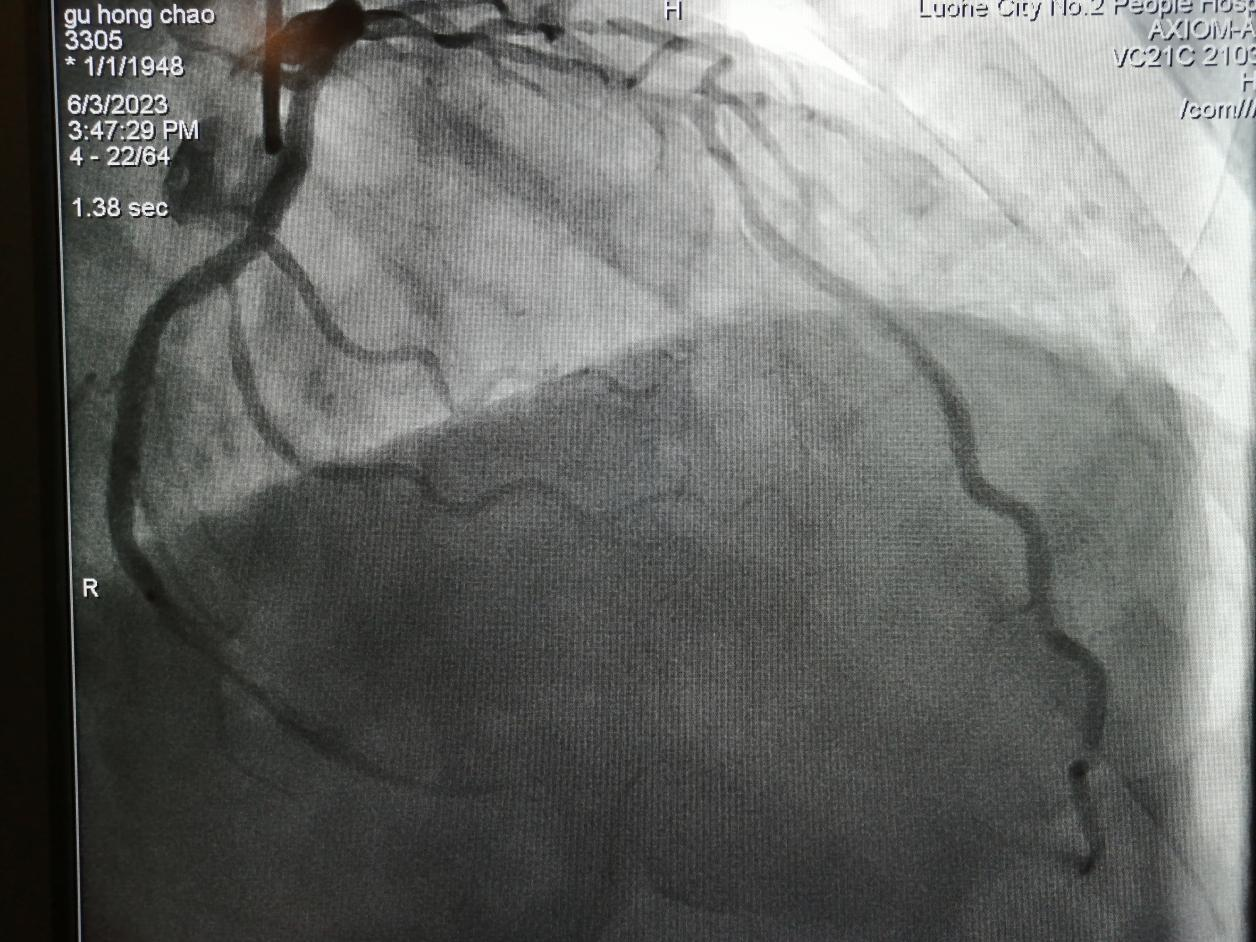

病例三

75歲的谷大爺,4年前行冠脈介入手術(shù)。近日,因“胸痛5天”入住心血管內(nèi)科,經(jīng)檢查冠脈造影發(fā)現(xiàn),前降支長段狹窄合并鈣化。

金叔宣教授帶領(lǐng)心血管內(nèi)科介入團(tuán)隊(duì)為谷大爺制定了個(gè)體化的手術(shù)治療方案,即行血管內(nèi)超聲,旋磨前降支,后置入心臟支架1枚。

術(shù)后,谷大爺胸痛癥狀得到有效緩解。

術(shù)前: